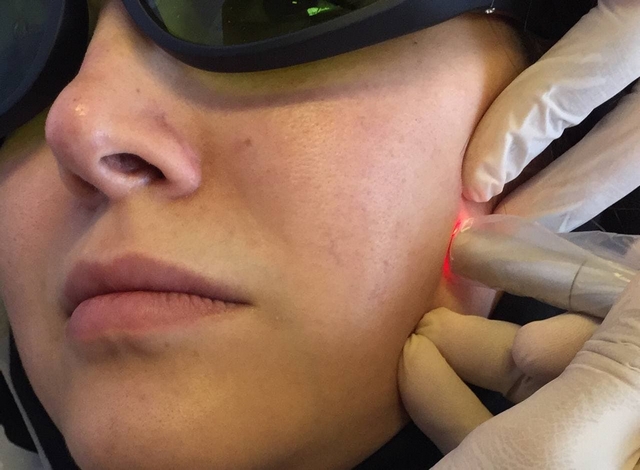

کاربرد لیزر در درمان اختلالات گیجگاهی فکی TMD در بیماران دارای اختلال گیجگاهی فکی که در هنگام باز و بسته کردن دهان در ناحیه کندیل مفصل صدا می دهد، در لمس نیز حساس است و محدودیت در بازکردن دهان و انحراف فک از جمله علائم آن می باشد کاربرد دارد... -